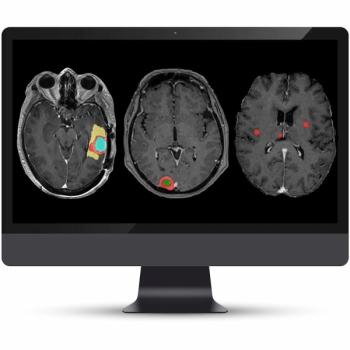

The addition of two new AI-enabled models for the latest version of the NeuroQuant Brain Tumor software facilitates automated tracking of the progression of brain tumors and meningiomas.